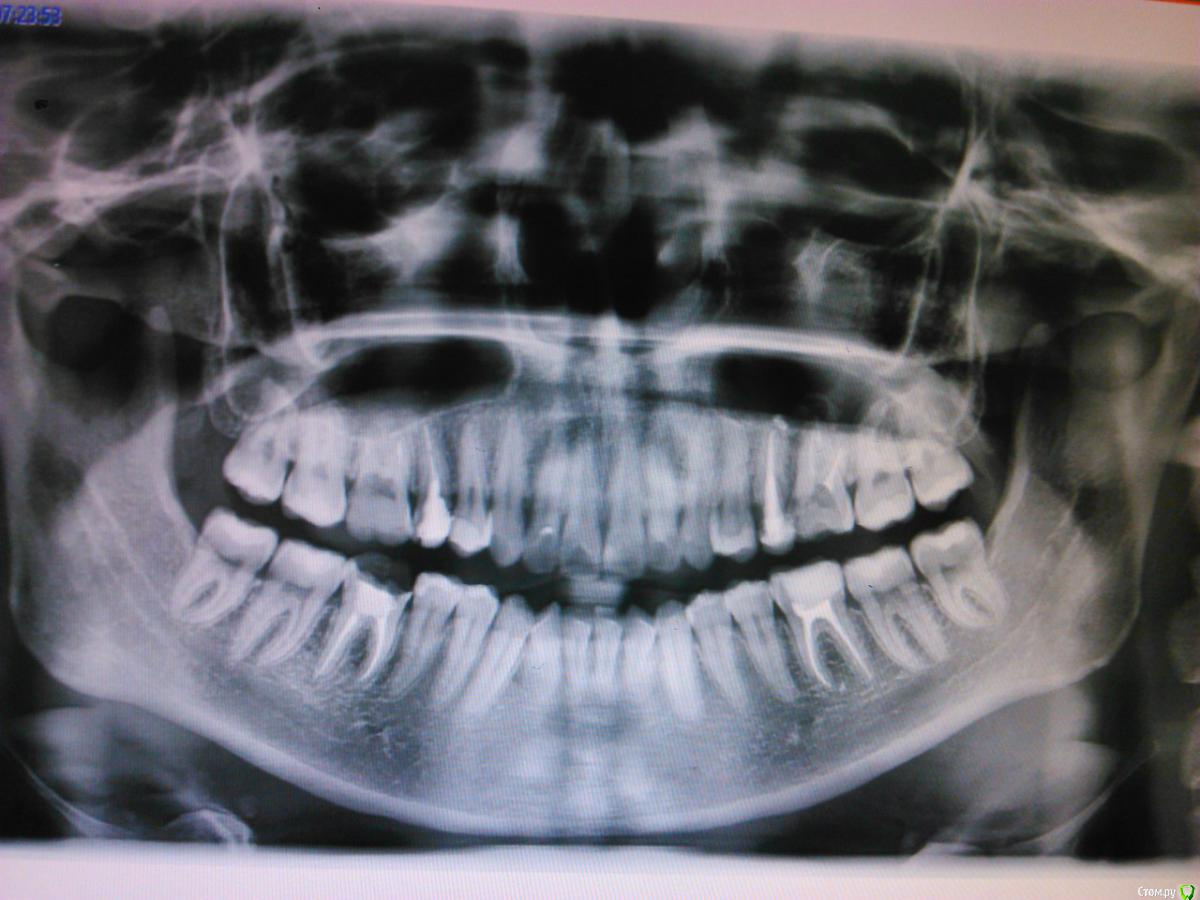

Vv4 Опубликовано 25 сентября, 2015 Поделиться Опубликовано 25 сентября, 2015 И так, что мы имеем. 46 у нас идет под вкладку культевую однокорневую. Принято решение ставить коронку из диоксида циркония.Из опыта по коронкам я имею только штамповку. Это моя первая серьёзная работа.Подскажите советом, есть ли особенность обточки культевой вкладки? Какие тонкости? Ничего если я обточу чуть больше, чем положено под цирконий? Это же не своя культя зуба. Вобщем жду каких-нибудь советов по этому поводу от специалистов имевших дело с такой ситуацией. Ссылка на комментарий

Vv4 Опубликовано 26 сентября, 2015 Автор Поделиться Опубликовано 26 сентября, 2015 Я так понимаю препарировать с уступом будете в первый раз..если вкладка будет изготовляться непрямым методом,то все очень просто:1.поросите техника изготовить вкладку и оставить чуточку больше места,чем это требуется под уступ для такой реставрации..2.т.к. вкладка будет изготовлена техником,вам будет проще..зафиксируйте вкладку и не торопясь,опираясь бором на контур вкладки формируйте уступ,т.е.опускайте ткани зуба,оставленные под уступ до уровня десневого края или чуть выше,для таких реставрации это приемлемо..т.к. тканей под уступ было оставлено больше,вам легче будет прочувствовать этот момент,потому что если бы техник оставил тканей как положено,вы бы "спилили"эти ткани до нуля,а в этом случае у вас есть место для маневра..Даже если получится уступ широким,думаю в первый раз это не критично,зато вы прочувствуйте и поймете как надо препарировать с уступом в др.раз..3.не оставляйте острых углов,чтобы не было внутреннего напряжения в реставрации..4.для окончательной полировки реставрации и сглаживания острых углов,если у вас нет повышающего наконечника,сбавьте обороты на турбином наконечнике на самой установке и полируйте бором с красной маркировкой,а далее резинками..5.когда будете препарировать под вкв,оцените остаточные ткани зуба..бывает такое,что остается тканей со всех сторон высотой 2 мм всего..в таком случае,при такой реставрации,можно просто все отполировать резинками и снять оттиск под вкв и все..далее зафиксировать вкв и сразу снять оттиск без препарирования..Спасибо за развернутый ответ. Да, вкладка будет изготовляться непрямым методом. У 46 зуба сохранена только щечная стенка высота её примерно 1.8 - 2 мм. На счет сразу снять оттиск без обточки не знаю... у меня в клиники все врачи точат вкладки перед тем как снимать оттиск. Ссылка на комментарий